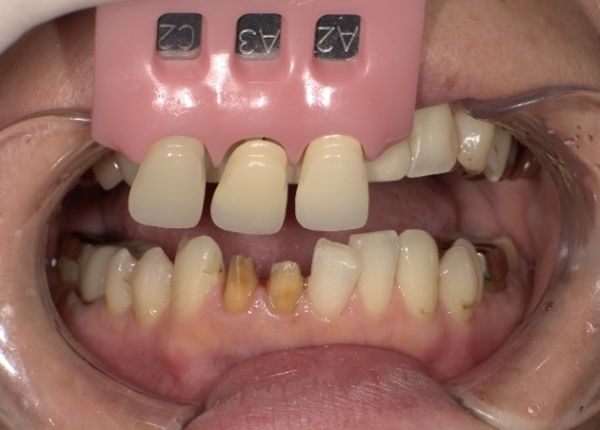

型取り、色合わせのための写真撮影を行い最終補綴へ移行しました。

今回の被せ物に関しては、セラミックでの治療なので、金属を使用していないため、歯と歯茎の境目に金属色が見えてくるなどのリスクもありません。セラミックの中でも、ジルコニアセラミックを使用することで色調だけでなく、汚れがつきにくく、強度もあり、長期的に使用可能な被せ物を装着することができます。また、ご自身の歯との色の違いを最小限にするように心がけました。

色調に関しては、写真を多数撮影して、提携ラボ歯科技工士さんへお送りし、色調の再現をお願いしております。

使用カメラに関しても技工士と同じものを使用する事で、色の誤差などを最小限に減らすよう工夫しております。